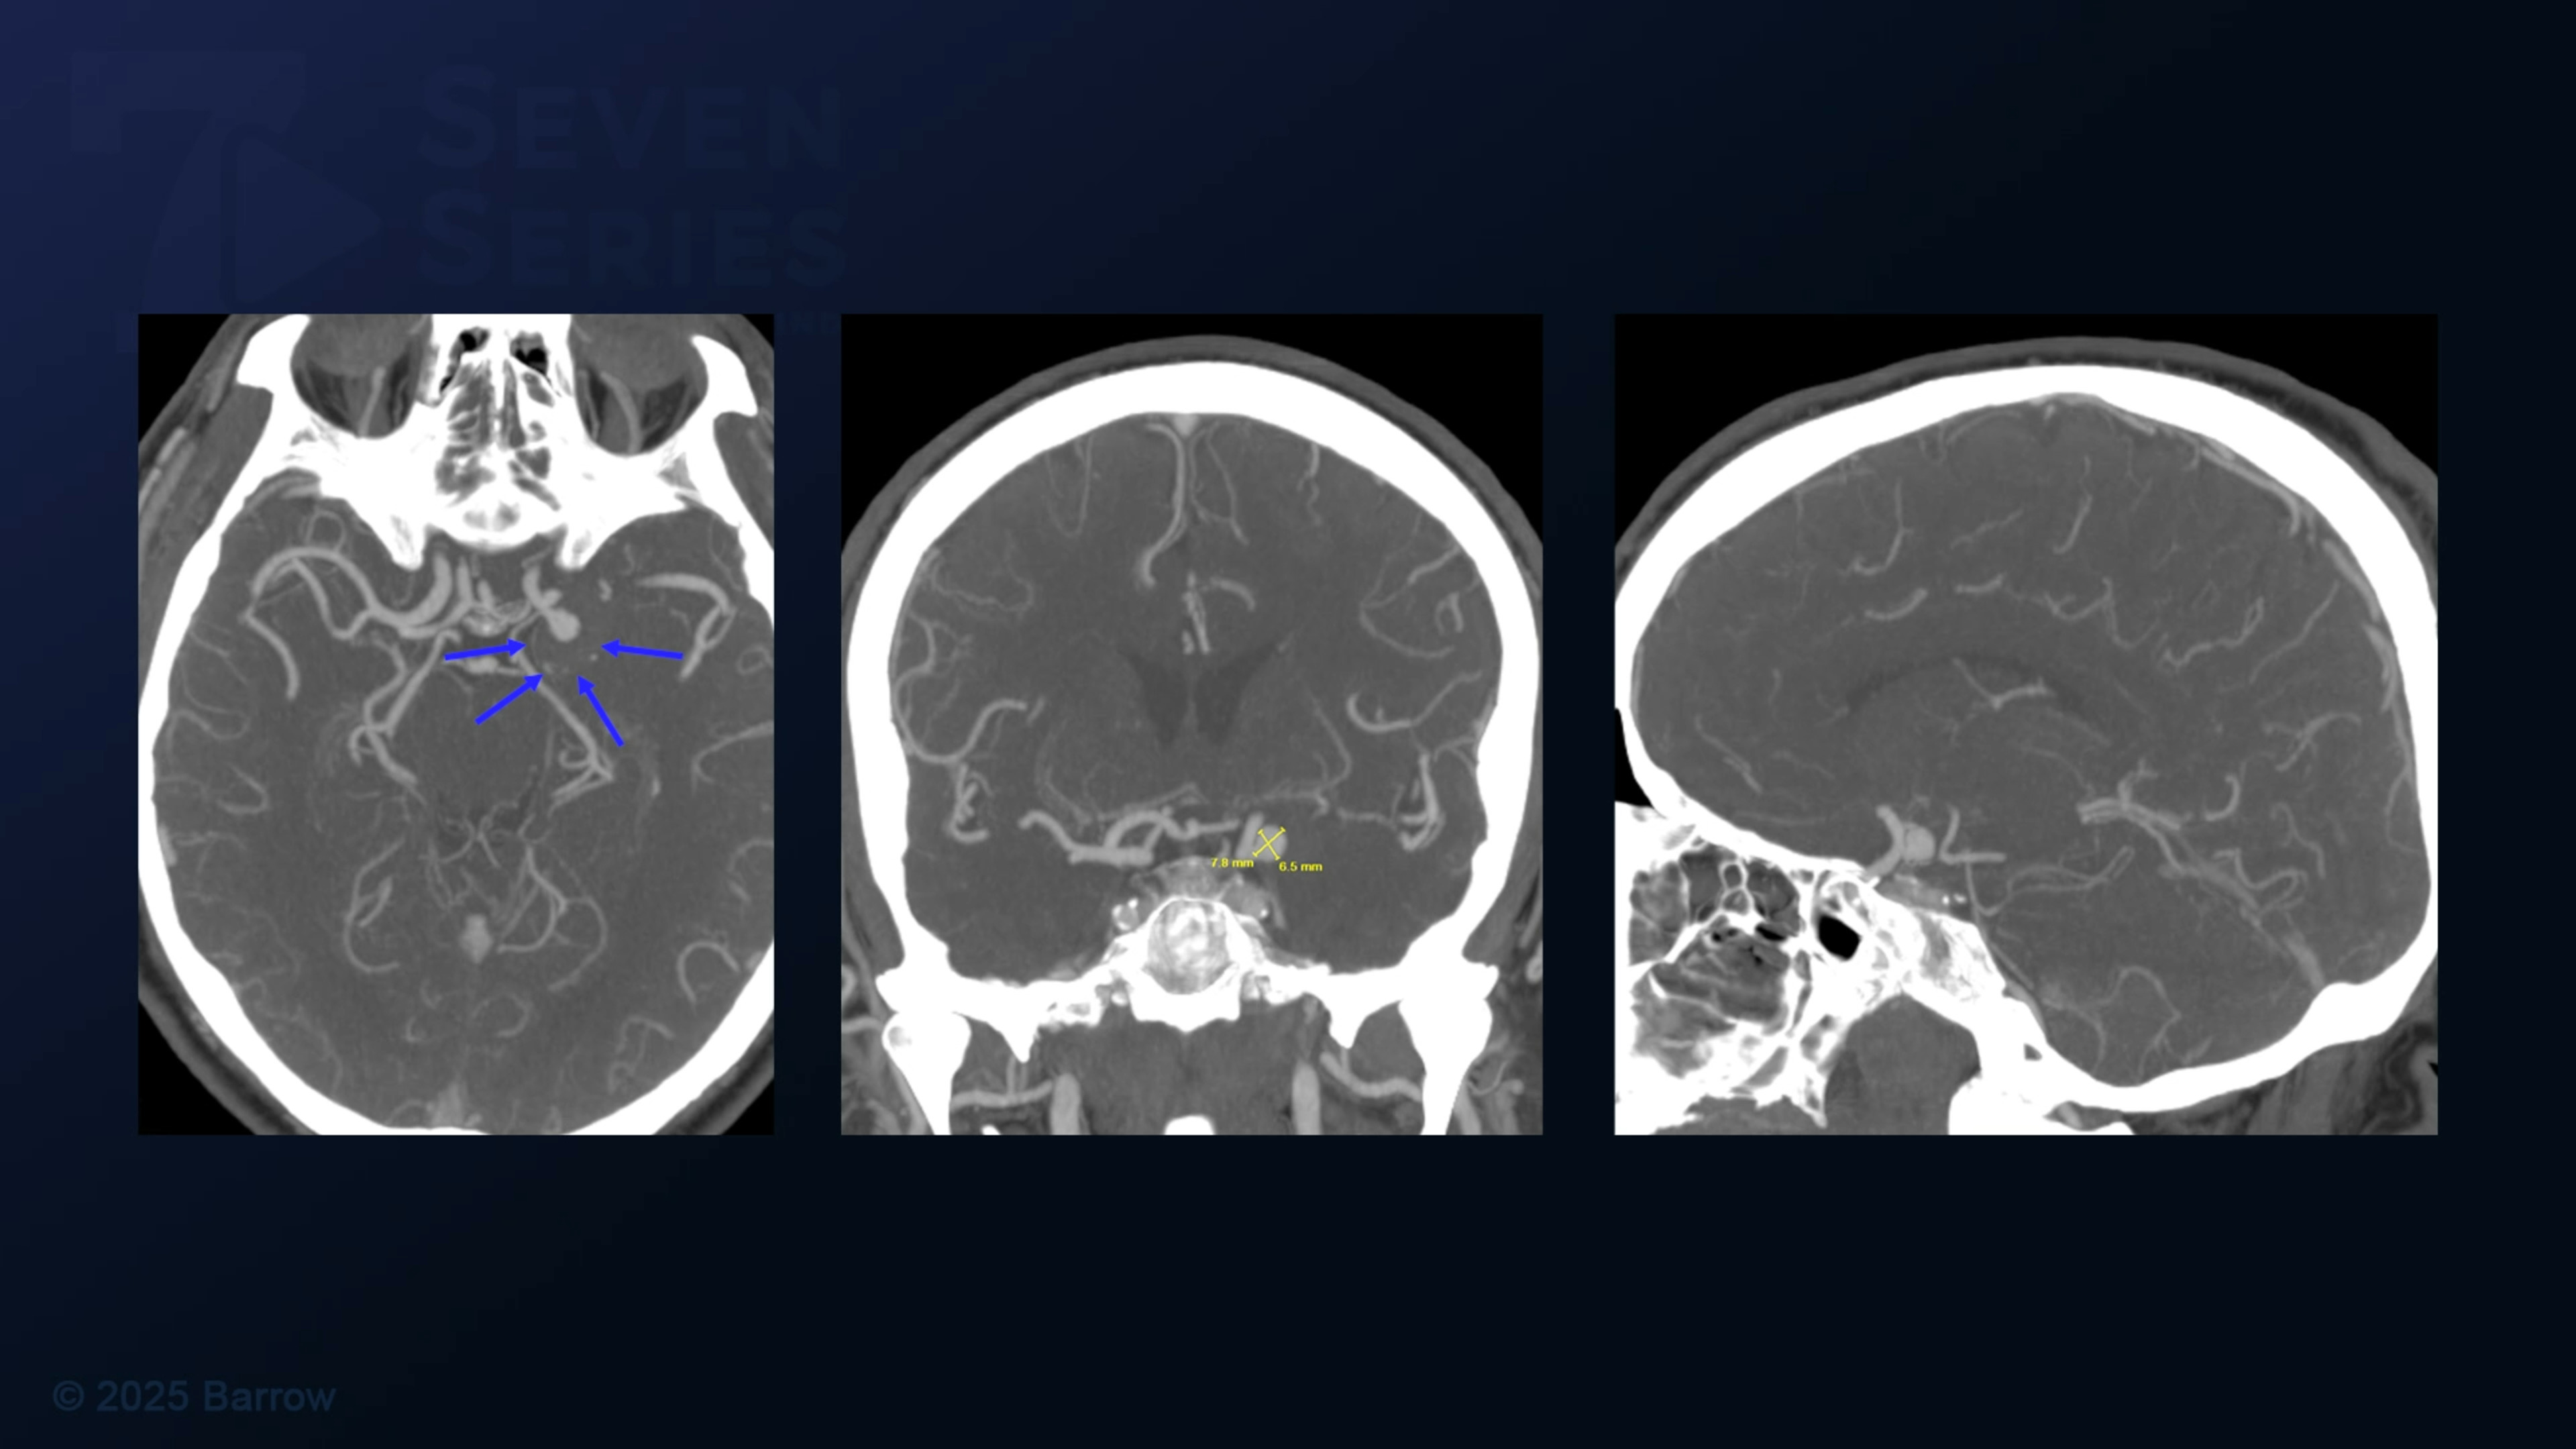

Episode 471 of Seven Series shows thrombectomy and clip reconstruction of a giant, thrombosed posterior communicating artery (PCoA) aneurysm.